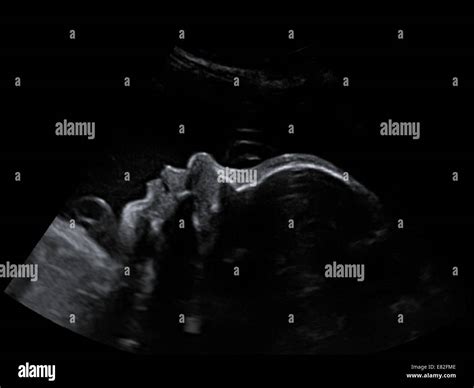

During the 32 weeks pregnant sonogram, you will lie on an examination table, and a gel will be applied to your abdomen. The sonographer will use a transducer to capture images of your baby. The procedure is painless and usually takes about 20-30 minutes. Here are some key aspects that will be checked during the scan:

• Baby's Growth: The sonographer will measure the baby's head circumference, abdominal circumference, and femur length to ensure that the baby is growing at a healthy rate.

• Placental Position: The position of the placenta will be assessed to ensure it is not covering the cervix, which could lead to complications during delivery.

• Amniotic Fluid Levels: The amount of amniotic fluid will be evaluated to ensure there is enough for the baby to move and develop properly.

• Baby's Position: The baby's position in the uterus will be checked to see if it is head-down, which is the ideal position for delivery.

• Anatomy Check: A detailed anatomy check will be performed to ensure that all organs and structures are developing normally.